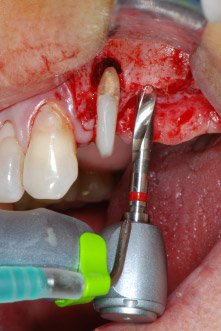

implant motor

Fig. 8: Rotary preparation of the implant bed short of the floor of the maxillary sinus at position 25, carried out with an updated implant motor.

IImplant beds were prepared at sites 25 and 26 with rotary instruments, used in a contra-angle handpiece with a 20 : 1 transmission ratio with an updated powerful implant motor (Implantmed, W&H) (Fig. 8).

The final preparation next to the sinus was again carried out with a piezoelectric instrument (Piezomed, insert S2).